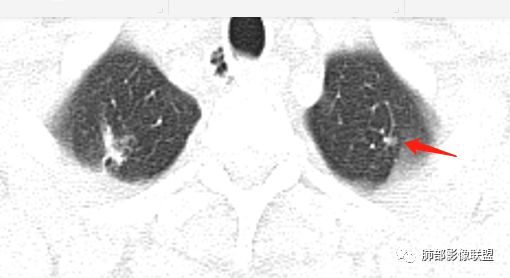

南边:2、不踏实的地方:GGO是不是容积效应所致?如果薄层,边界清楚GGO,就考虑继发瘢痕癌

因此我们需要的是:薄层、重建,看GGO边缘、看整体形态

瘢痕癌就需要薄层、重建观察更妥当

南边:瘢痕癌就需要薄层、重建观察更妥当

生来征服~浪子:部分层面彭隆的挺明显。

Coke with ice:瘢痕癌+1

^_^果:支气管有堵塞

wonderful:结核肯定有 疤痕癌可能?

结果:结核合并真菌(曲霉菌)感染